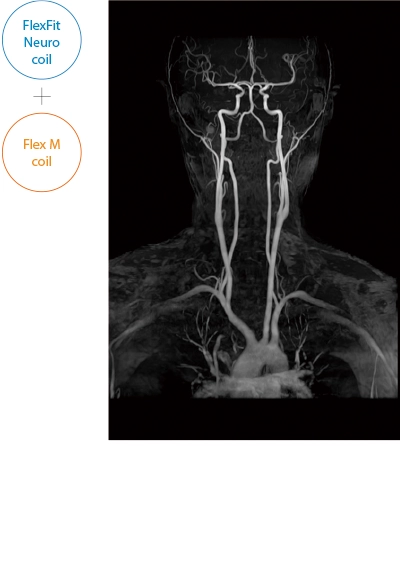

The ECHELON Synergy ZeroHelium is equipped with a flexible head and neck coil that allows one-action setup via sliding installation, as well as a Flex coil that provides wide and flexible coverage of the imaging area. This enables flexible adaptation to different part of body.

“OpenHead Mode“ which allows imaging without covering the anterior side of the coil over the patient’s face is equipped. By not obstructing the patient’s field of vision, this mode helps reduce the psychological stress associated with the imaging process.